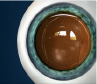

Las EVO Visian ICL enfocan la luz correctamente en la retina, de una forma similar a las gafas y las lentes de contacto. Las EVO Visian ICL se colocan directamente detrás del iris (la parte coloreada del ojo) y delante del cristalino. De este modo, las EVO Visian ICL enfocan la luz correctamente en la retina, lo que ayuda a crear una visión clara de lejos.

Las EVO Visian ICL se colocan detrás del iris y delante del cristalino, por lo que son indetectables. Solo un médico capacitado y que utilice la instrumentación necesaria podrá saber que se ha sometido a una intervención refractiva.